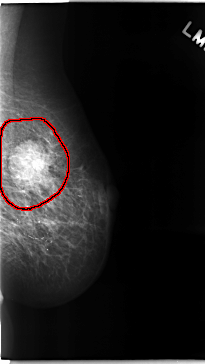

C_0111_1.LEFT_CC

LEFT_CC LINES 4744 PIXELS_PER_LINE 2528 BITS_PER_PIXEL 12 RESOLUTION 50 OVERLAY

FILE: C_0111_1.LEFT_CC.OVERLAY

TOTAL_ABNORMALITIES 1

ABNORMALITY 1

LESION_TYPE MASS SHAPE LOBULATED MARGINS MICROLOBULATED

ASSESSMENT 5

SUBTLETY 5

PATHOLOGY MALIGNANT

TOTAL_OUTLINES 1

BOUNDARY